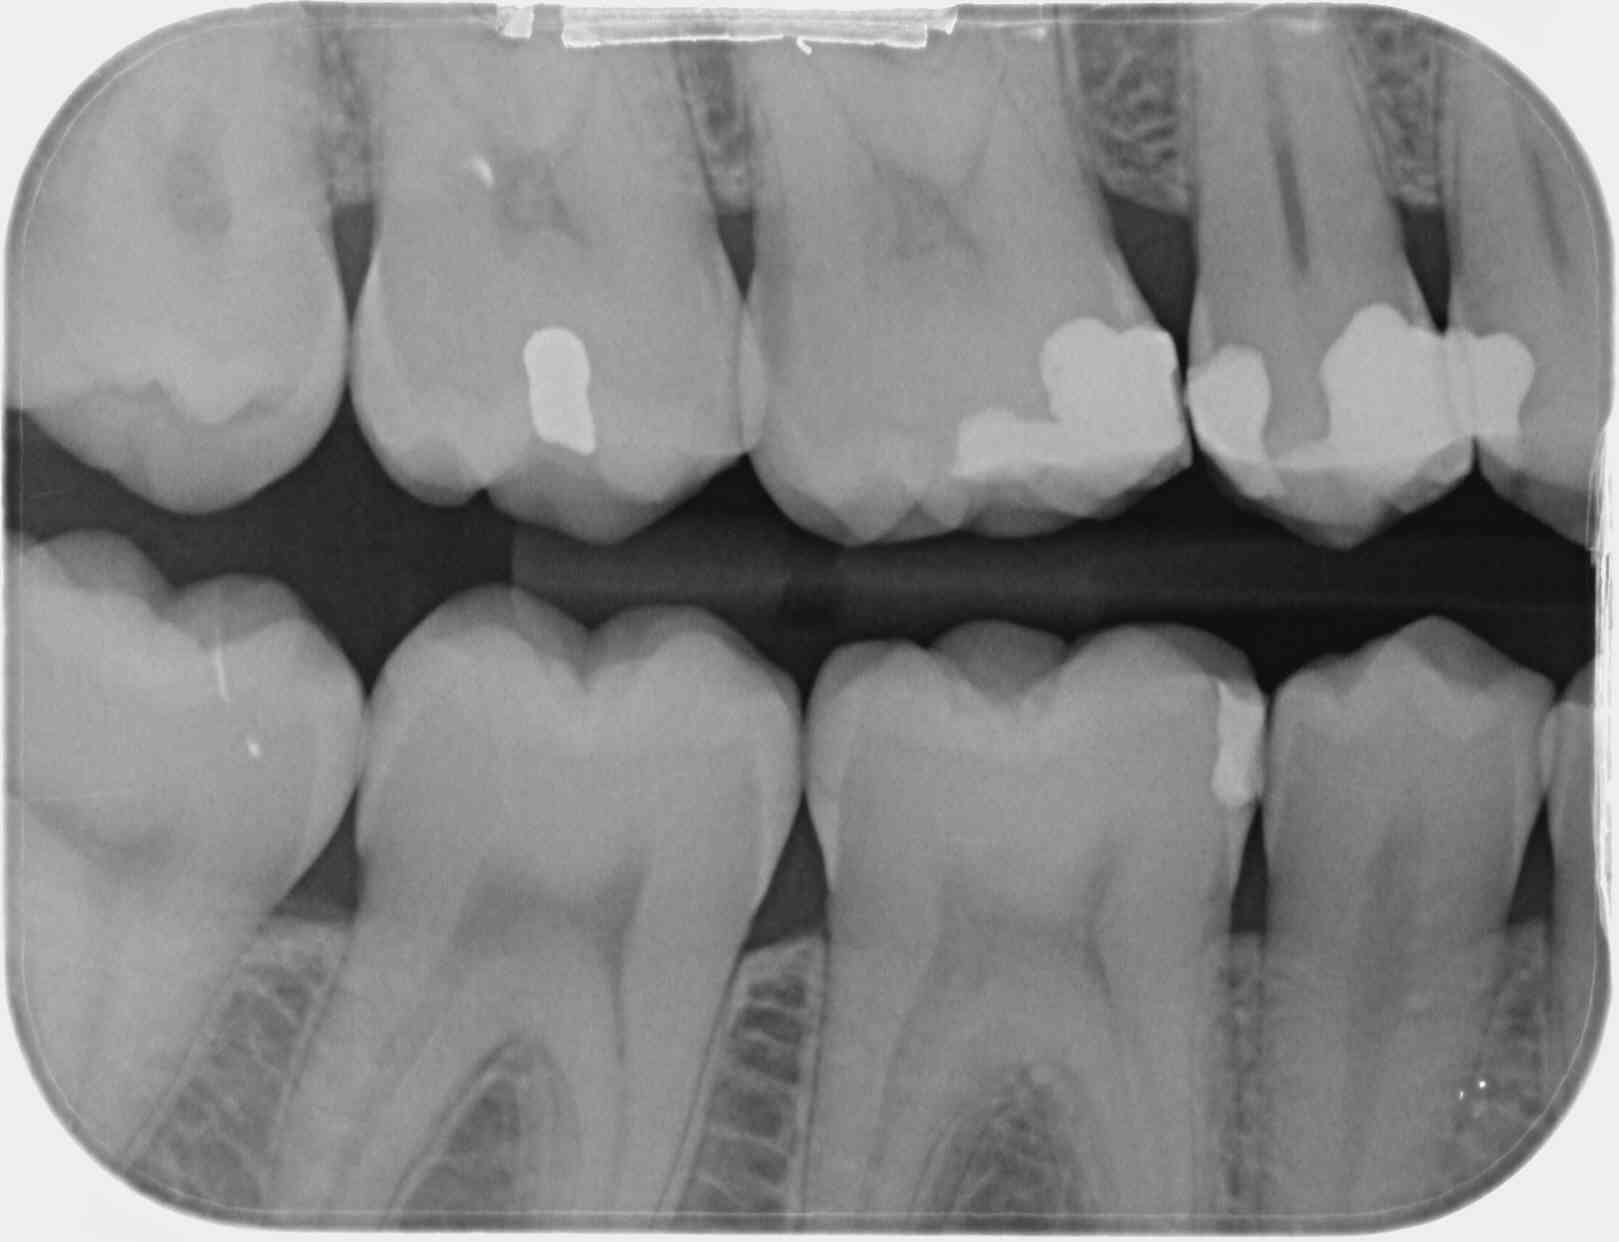

par contre les retro coronaires doivent montrer le septum et les couronnes et dans la REALITE de mes yeux il y a bien DEUX secteurs visibles par cliché

les secteurs étant décrits aussi noir sur blanc

Bop... en cas de controle d'activité, le CDC va ouvrir le guide de la HAS:

"Un cliché rétrocoronaire doit montrer les couronnes des dents antagonistes

radiographiées..."

1 secteur en BW: c'est 3 couronnes ET leurs antagonistes...

Mais dans l intitulé du code de 2bw on parle pas du nombre de clichés mais du nombre de secteurs.

Du coup, ce qui est important c est la définition d un secteur.

On se tape pas trop de ce que dit la HAS puisque c est dans les recommandations de la HAS que sont les réponses en cas de contrôle d activité.

Et la clé de cette "énigme" c est que 1 secteur en bw c est 3 couronnes ET leurs antagonistes

1 secteur en bw c'est 3 couronnes et leurs antagonistes... Et pas juste 3 couronnes.

on ne code pas des clichés

on code des secteurs

et ce "quel que soit le nombre de clichés"

tu t'es fait rouler dans la farine

ici, je vois "radiographiés"

4 secteurs

en mode rétro coronaire

dont on voit 4 fois les couronnes + les septum

( = secteur codifié )

+ les couronnes dentaires du secteur antagoniste

( indispensable )

demande lui si ta description des ces 2 "clichés" est conforme à la CCAM